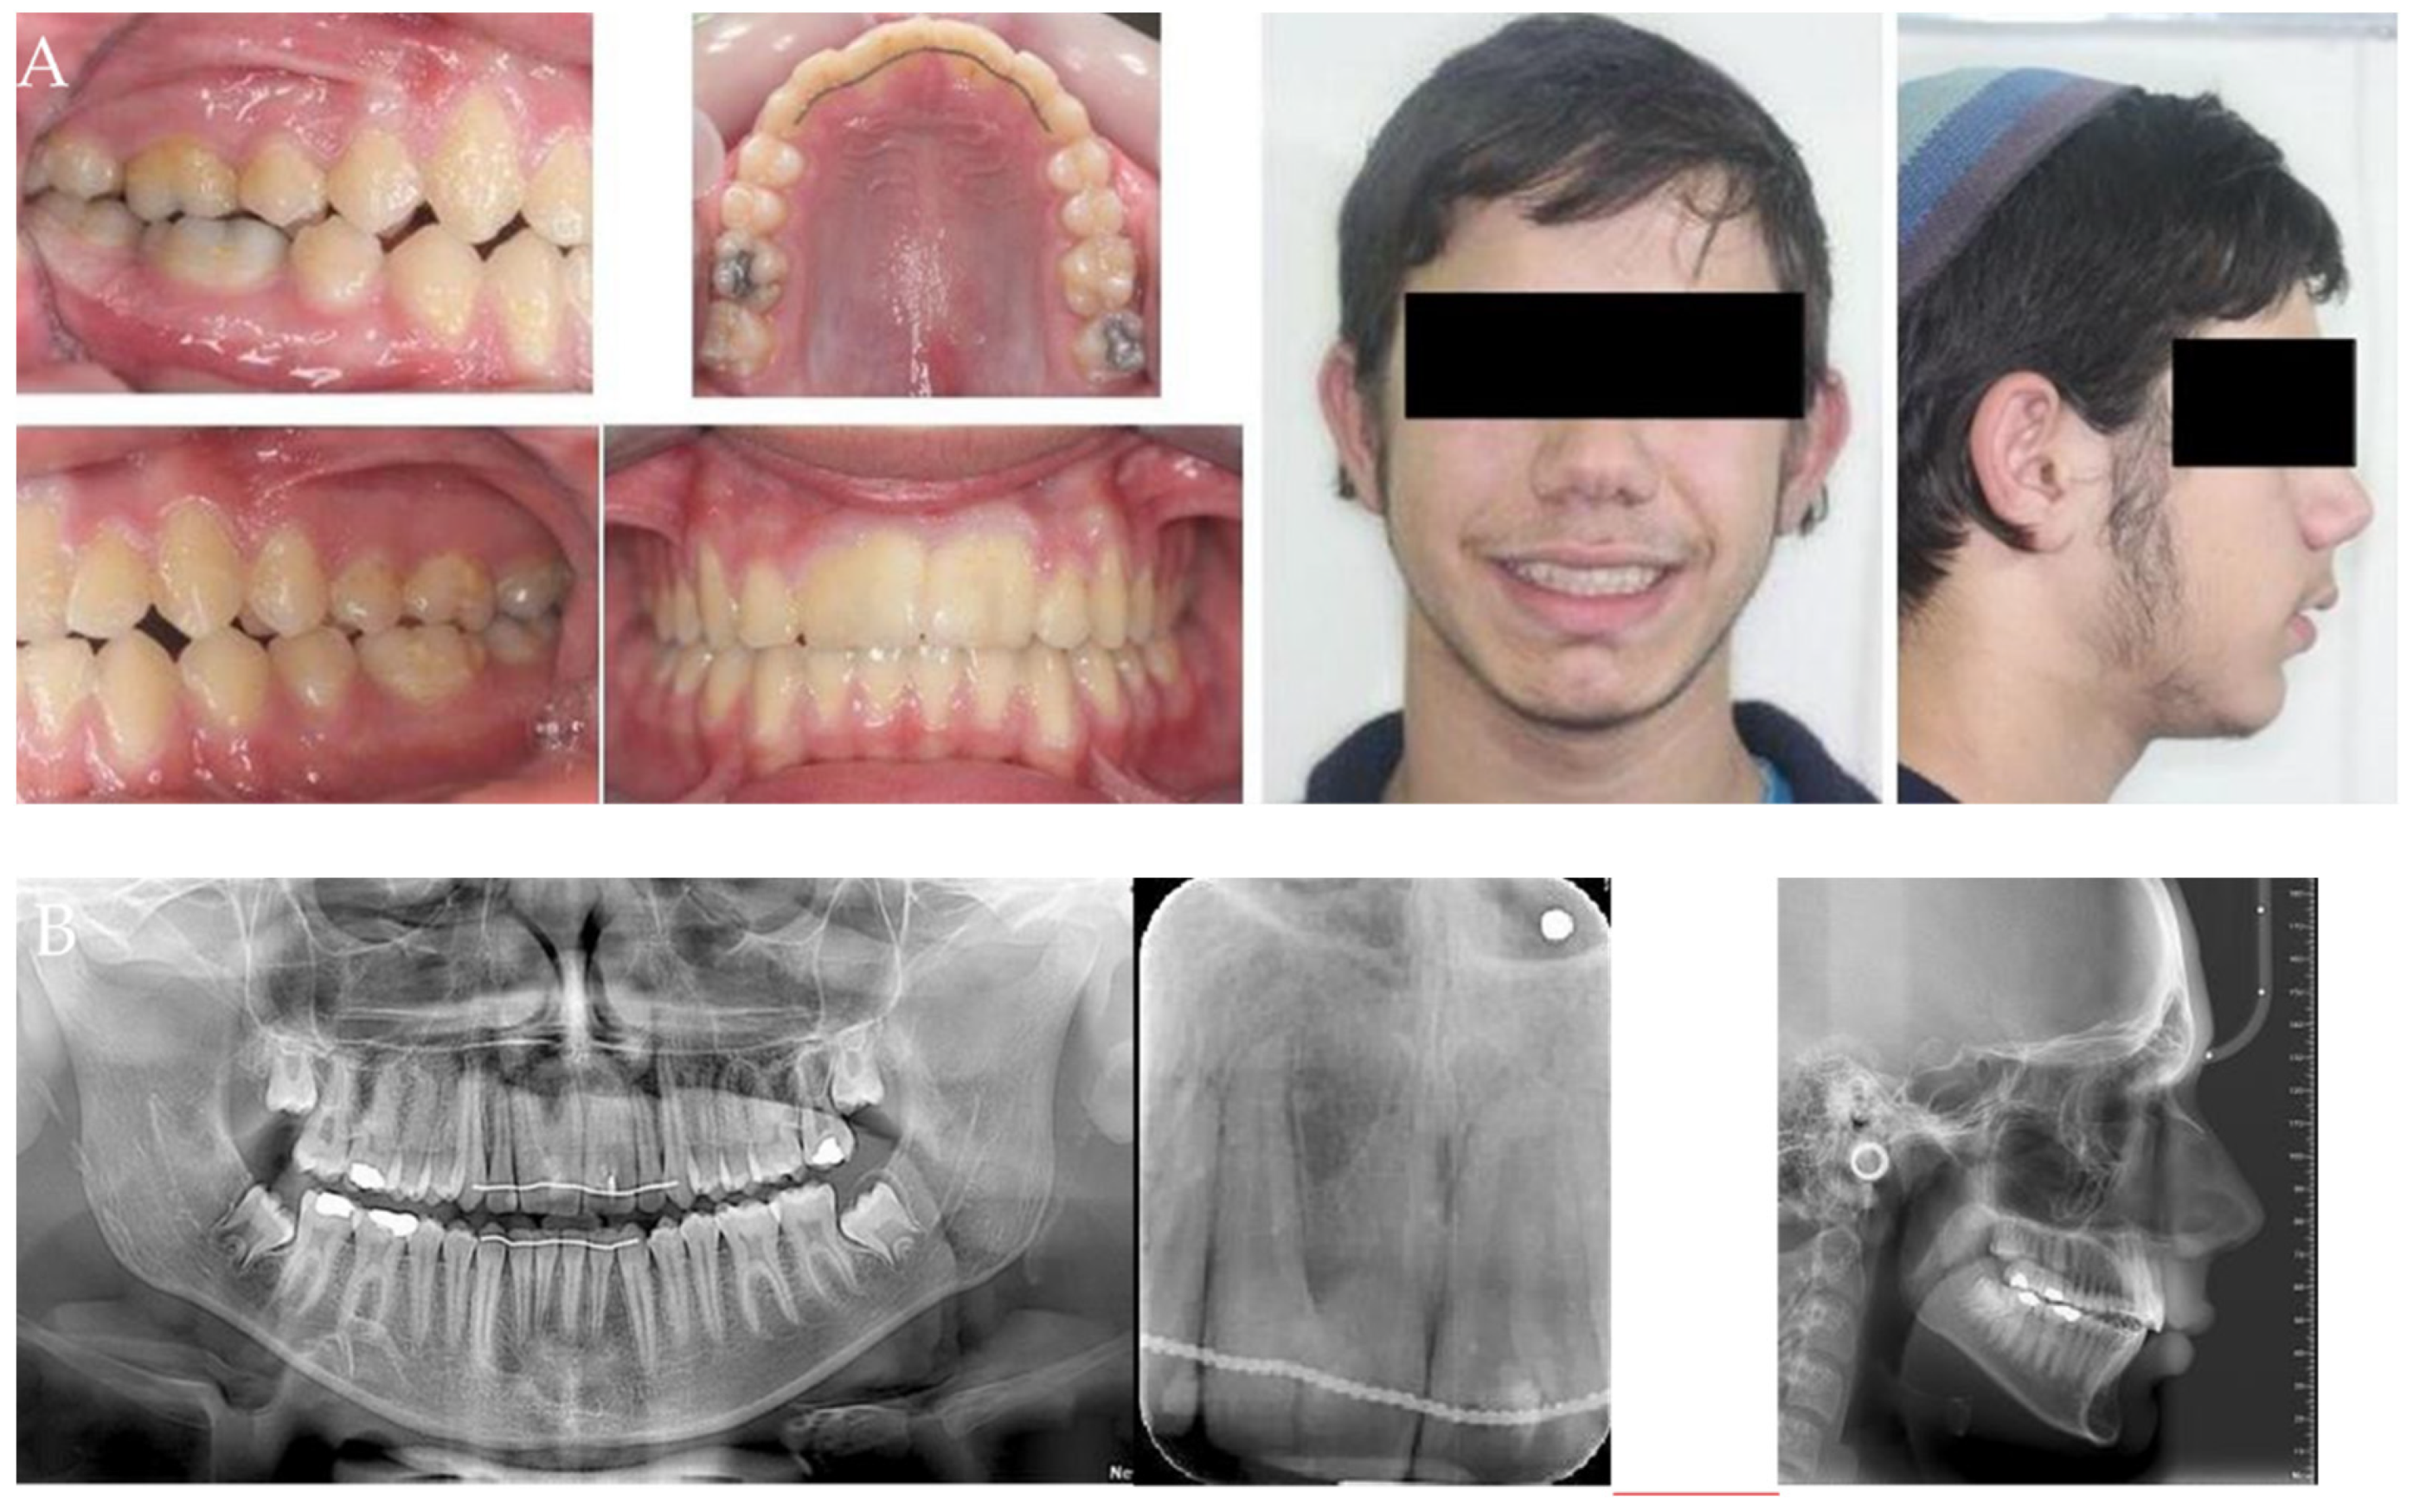

Geminated Maxillary Incisors: The Success of an Orthodontic Conservative Approach: 15 Years Follow-Up Study

2. Materials and Methods

- Patients

- Gemination Characteristics